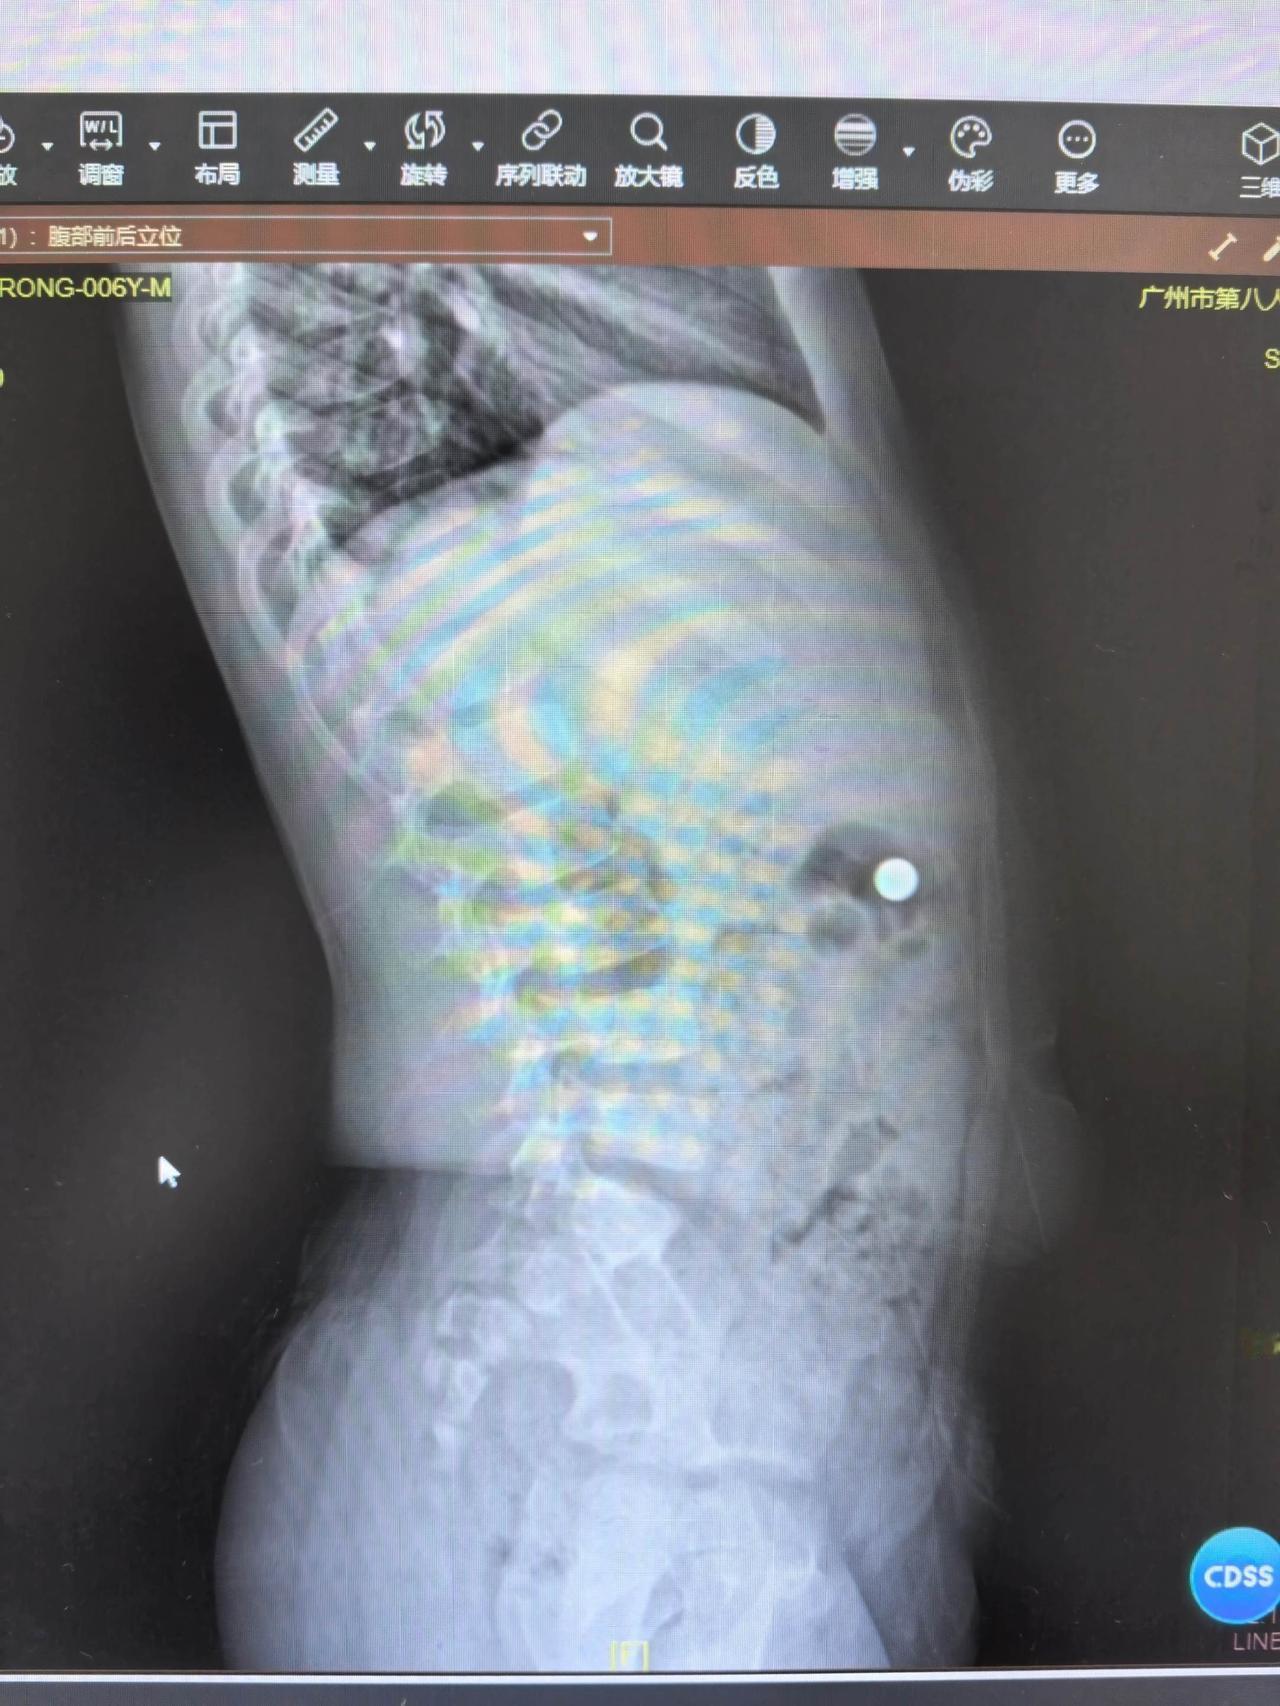

你们猜猜 这个小家伙 把什么吃到肚子里去了?

电池